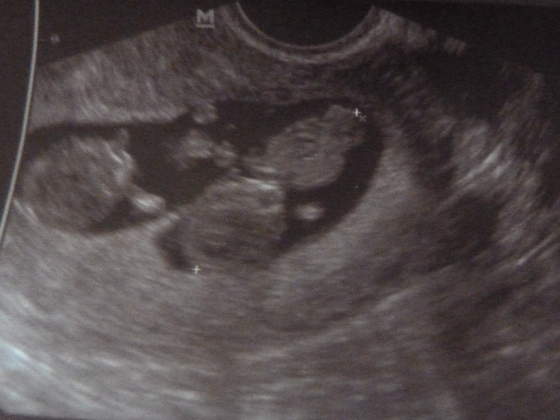

stokrotta śliczny-widać już rączki :-) mój też już wymachiwał :-)